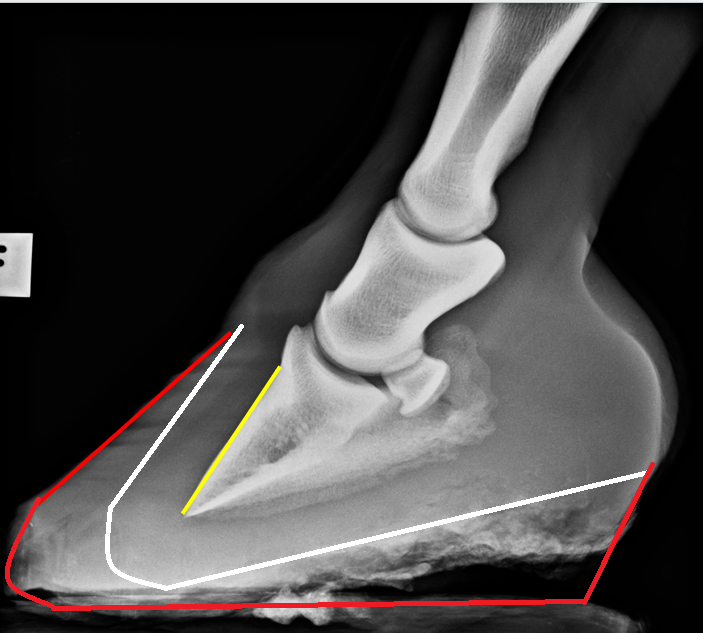

Hooves suffering coffin bone rotation can look like this. Long toes and high heels. If this is tradition or fashion doesn’t matter. It is very common and very wrong.

With some trimming and some time, the hoof would soon become nice-looking and healthy again. My white line shows the wanted hoof shape, and as you can see, it is absolutely doable. The horse wasn’t standing on his toes when being X-rayed, so the black part under the heels is hoof wall that was of too poor quality to show up on a radiograph (just like you can’t see the digital flexor tendons in this picture (tendons are just not dense enough).

If you understand that the problem is the hoof capsule — not the coffin bone — then “coffin bone rotation” is easy to rehabilitate. There is truly no reason to fail.